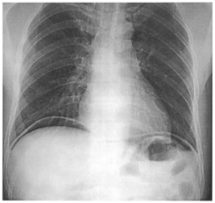

75 某日某甲感到上腹疼痛,次日疼痛更為嚴重。體檢 發現病人腹部有壓痛及反彈痛,腹肌僵直。站立胸 腹部 X 光照相如圖所示。則最可能的診斷是:

(A)腸胃穿孔(GI tract perforation) (B)腸堵塞(Intestinal obstruction) (C)腹膜炎(Peritonitis) (D)肝膿瘍(Liver abscess)